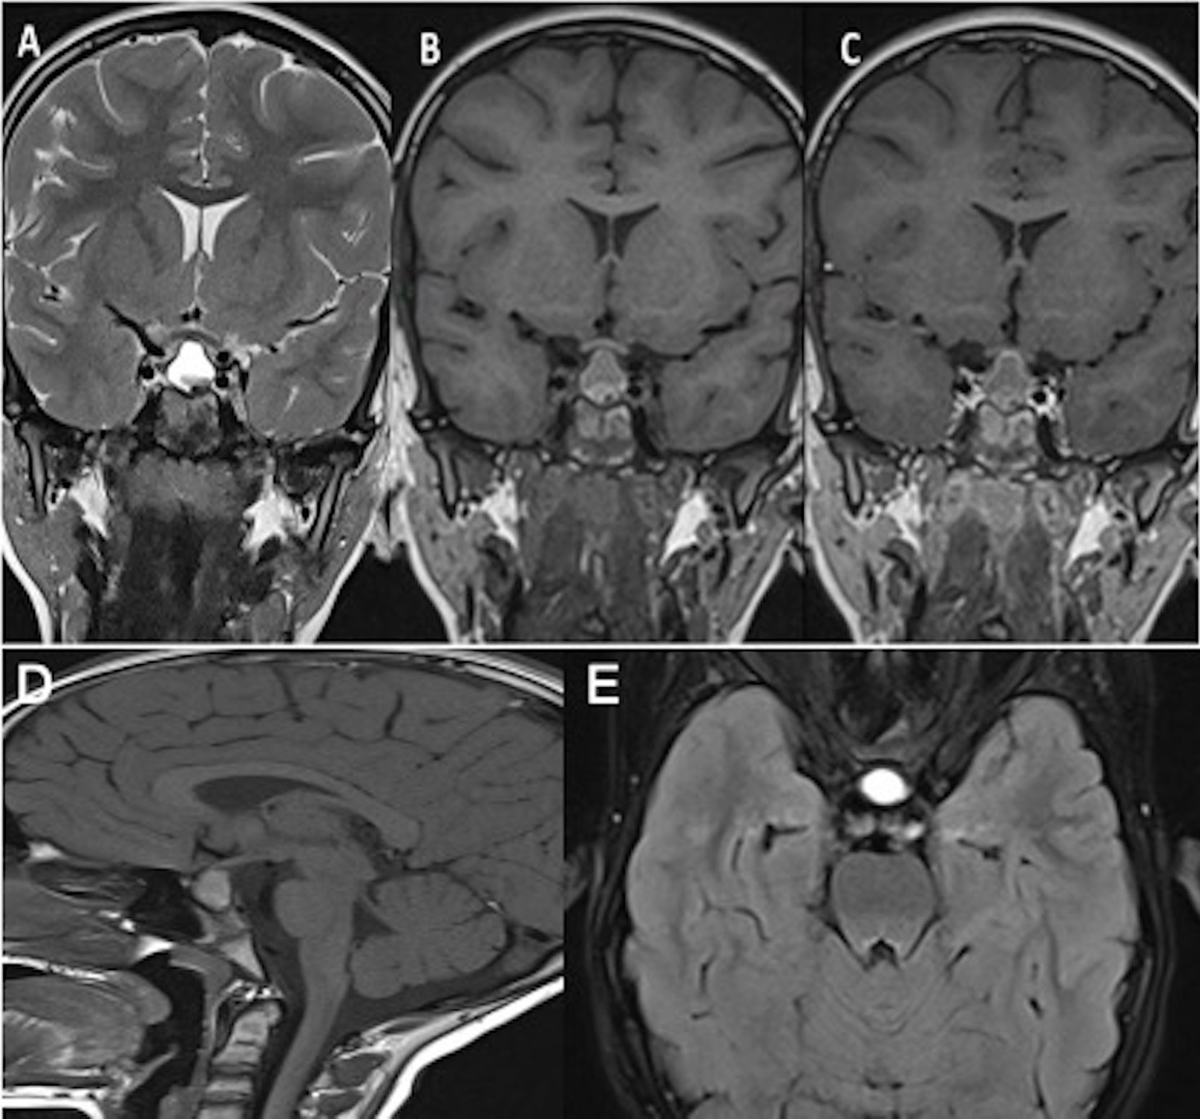

Figure 5

Ten-year follow-up of the same patient: Coronal T2WI (A), T1WI (B), post-contrast T1WI (C) and sagittal T1WI (D) show an increase in size of the lesion as well as the intracystic nodule.